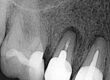

Para lograr un buen sellado tridimensional se usa la técnica de calor contínua con el sistema Fast Pack. Para el relleno del tercio coronal se utiliza el sistema Fast Fill de inyección de gutapercha fluída. (Fig. 4 y 5)

En las imágenes del microscopio puede observarse el resultado de la obturación y su posterior revisión a los 12 meses. (Fig 6 y 7)

Fig. 4: Conometría donde podemos ver la disposición de la gutapercha en el interior del sistema de conductos.

Fig. 6: Imágenes al microscopio óptico y radiografías, donde podemos observar el sellado tridimensional del entramado radicular.

Fig. 7: Radiografía de revisión 12 meses después